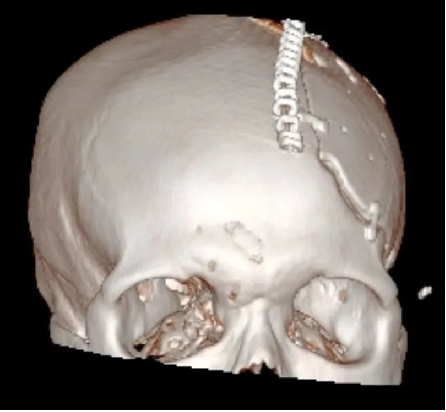

术前: